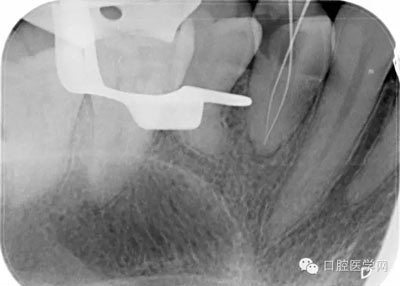

第五步:確定根管長度,臨床上常用方法為根測+X片+吸潮紙尖法。

根測法:用不銹鋼K銼插入根管直至有阻力部位,夾入根管測量儀器測量,一般距離根尖顯示0.5MM為工作長度。

X片法:X線片上可以清楚看到根管銼插入根管的深度,但因看到的是解剖性根尖,而根尖孔大多數(shù)開口于側(cè)方,所以X線片 到達(dá)根尖時,實際是超出了。數(shù)據(jù)顯示根尖孔距離根尖可以從0.5mm-3mm之間。

(我的助手是拍個X片就像是段譽(yù)練的六脈神劍,時靈時不靈。不過這張片,我還是覺得美呆了。)